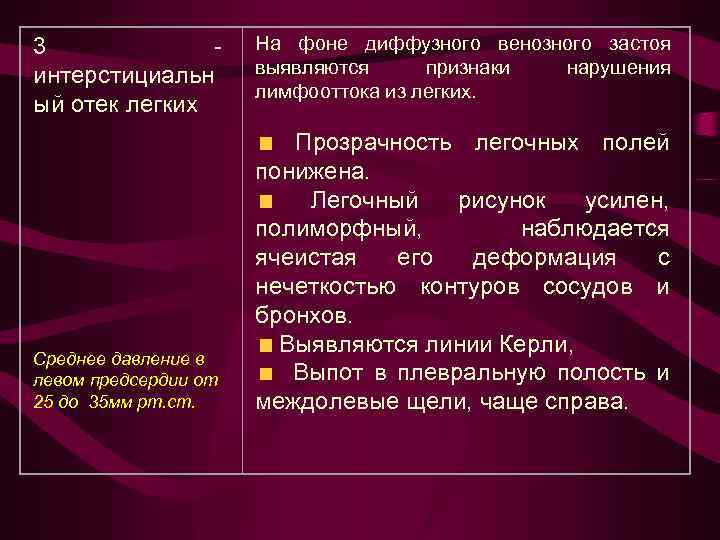

3 - интерстициальн ый отек легких Среднее давление в левом предсердии от 25 до 35 мм рт. ст. На фоне диффузного венозного застоя выявляются признаки нарушения лимфооттока из легких. Прозрачность легочных полей понижена. Легочный рисунок усилен, полиморфный, наблюдается ячеистая его деформация с нечеткостью контуров сосудов и бронхов. Выявляются линии Керли, Выпот в плевральную полость и междолевые щели, чаще справа.

3 - интерстициальн ый отек легких Среднее давление в левом предсердии от 25 до 35 мм рт. ст. На фоне диффузного венозного застоя выявляются признаки нарушения лимфооттока из легких. Прозрачность легочных полей понижена. Легочный рисунок усилен, полиморфный, наблюдается ячеистая его деформация с нечеткостью контуров сосудов и бронхов. Выявляются линии Керли, Выпот в плевральную полость и междолевые щели, чаще справа.